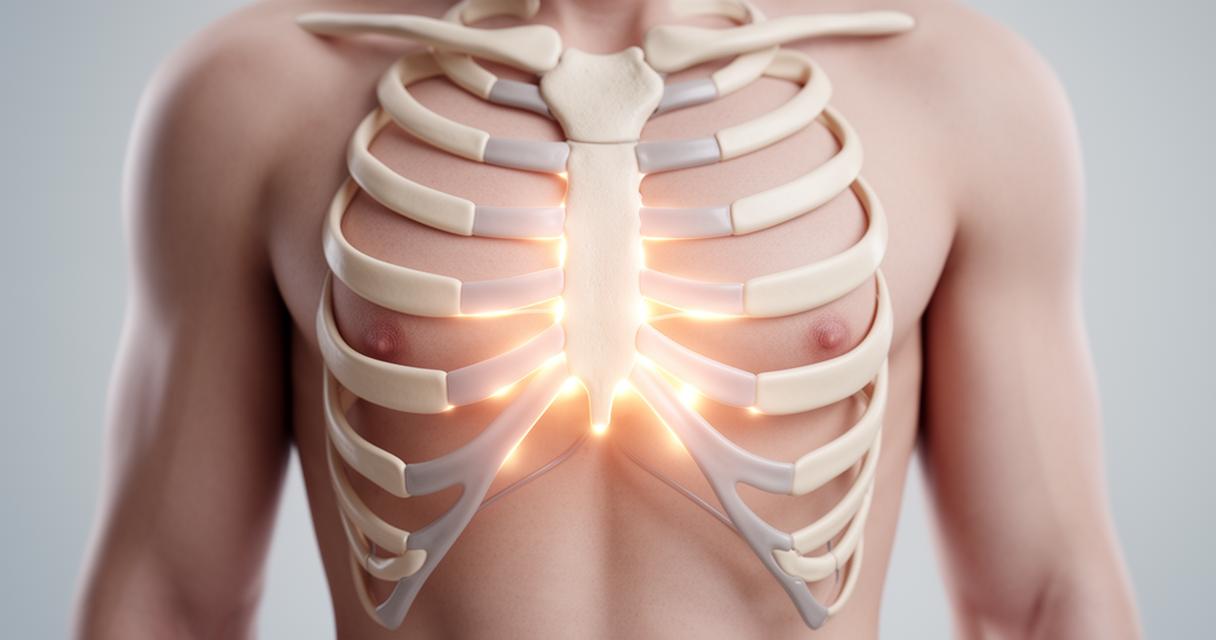

Notre cage thoracique est composée de plusieurs organes importants pour assurer notre survie, le coeur en fait partie. Mais cet organe peut tomber malade à cause de plusieurs raisons, dont le stress qui cause une pointe au coeur qui est extrêmement désagréable. Pour tout savoir sur cette pointe au niveau de la poitrine, on vous invite à lire notre article jusqu’au bout.

La manifestation d’un problème cardiaque peut être une douleur diffusée dans le corps ou localiser dans un seul endroit du corps. En outre, il y a aussi le mal qui s’intensifie variablement ou la douleur aiguë ou persistante dans la poitrine. En général, la douleur se manifeste comme une pointe au cœur.

Il faut noter que le stress aigu se manifeste par une émotion intense et soudaine et a un impact direct sur le fonctionnement du cœur. En effet, l’anxiété provoque une accélération du battement de notre cœur, et cet événement peut causer une obstruction des vaisseaux sanguins et va déclencher des douleurs thoraciques. Ces dernières sont causées par une angine de poitrine ou un infarctus du myocarde et peuvent conduire à un arrêt cardiaque.

Pour l’anxiété chronique ou à long terme, elle a plusieurs causes, dont l’insomnie, les troubles de vigilance, mais aussi des douleurs dans la cage thoracique. Une pointe au cœur passagère ne provoque pas un risque grave, mais on vous conseille quand même de consulter un médecin qui va vous demander de faire un examen.

On confond souvent le problème cardiaque avec le point au cœur, voilà pourquoi il faut consulter le médecin. Mais comment être sûr que c’est vraiment le syndrome de point au coeur ? Un examen cardiaque doit être fait pour que votre médecin soit sûr de ce qui vous arrive réellement.